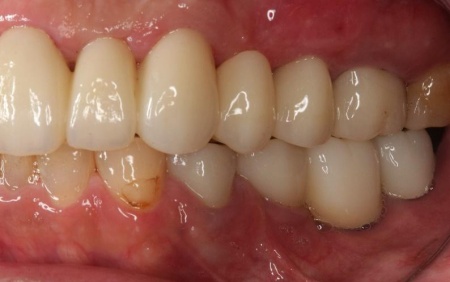

50代男性 バランスが崩れた噛み合わせをインプラント治療と被せ物治療で改善した症例

拝見したところ、右上奥歯4本が欠損しており、その影響で全体の噛み合わせのバランスが崩れていました。

加えて、噛んだときに上下の歯の中心がずれており、顔貌のゆがみにもつながっています。

欠損部が多い状態が長期間続いたことで噛み合わせが低く、新しい歯を入れるための高さも不足していました。

また、右上前歯も1本欠損しており、両隣の歯を土台として橋を渡すように連結した被せ物「ブリッジ」が装着されていましたが、土台となっている右上前歯2本(中切歯、犬歯)が割れており、温存が難しい状態です。

さらに、劣化してうまく適合していない被せ物、詰め物、既存のインプラントが複数見られ、これらも噛み合わせを乱す原因となっていました。

加えて全体的に歯周病も進行しており、骨が溶けている部分も確認できます。

インプラントが骨にしっかりとなじんだことを確認したら、白くて強度の高い人工歯「ジルコニアクラウン」を装着しました。

左下奥歯1本、右下奥歯2本に装着されていた古い被せ物はすべて外し、ジルコニアクラウンと交換しました。